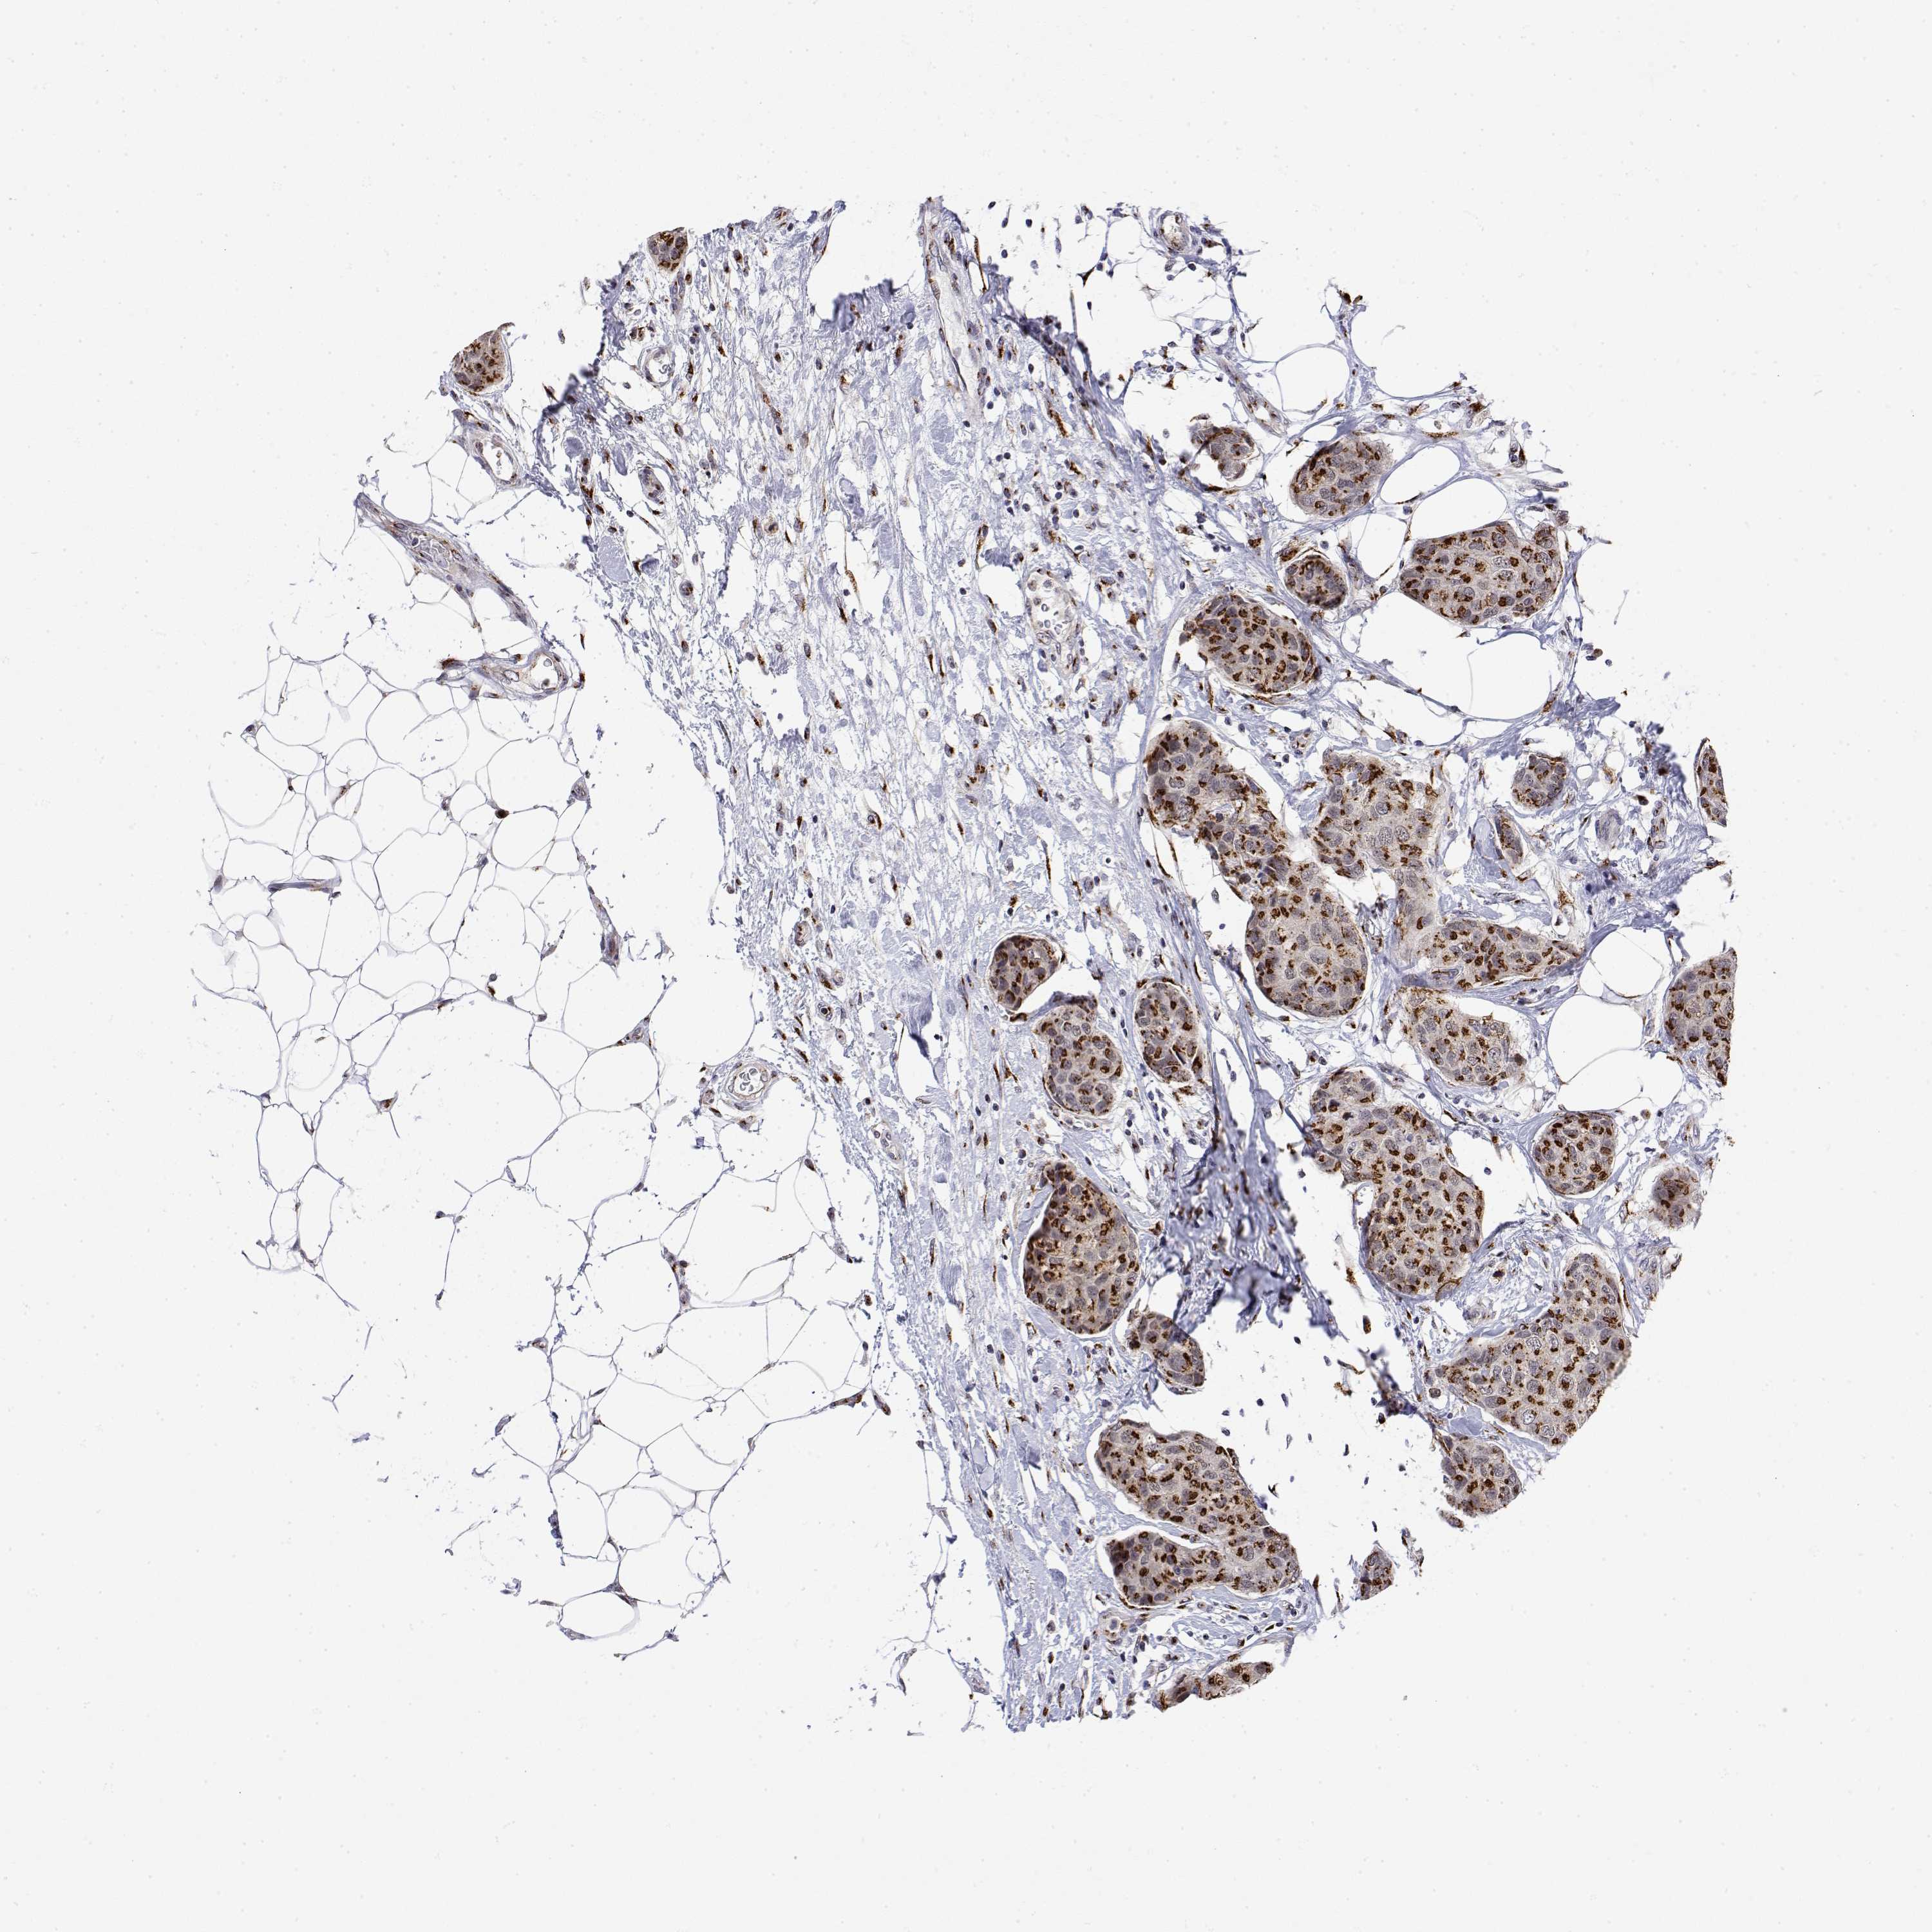

BRCA TCGA BRCA VALIDATION PROTEIN EXPRESSION